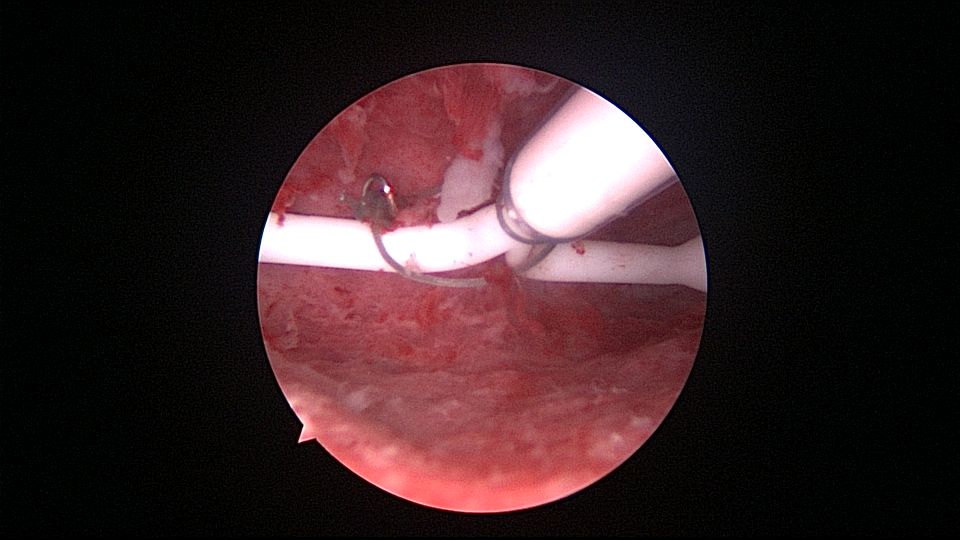

患者35岁,G5P2,剖宫产2次,异常子宫出血4年,外院诊刮无异常。2024年11月行宫腔镜检查,子宫前位,宫深8cm,宫腔形态正常,宫内膜正常,双侧输卵管开口可见,曼月乐尾丝连接环与不锈钢挂钩,将环固定于宫底肌层,取内膜送病检。病检为血凝块中见破碎增殖期样子宫内膜腺体。2024年12月复查B超,曼月乐位置正常,环顶端距宫底1.9cm。